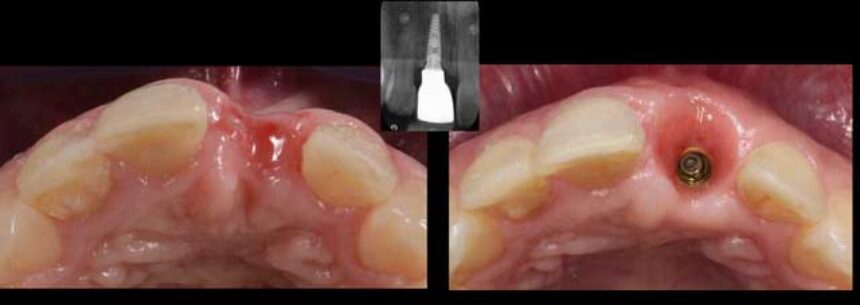

Η εξαγωγή ενός δοντιού στην πρόσθια αισθητική ζώνη αποτελεί μεγάλη αισθητική παρέμβαση καθώς η κατ’ όγκον απορρόφηση ιστών είναι αναπόφευκτη. Ο τρόπος αντιμετώπισης του μετεξακτικού φατνίου, ο χρόνος τοποθέτησης του η των εμφυτευμάτων και η διαχείρηση των μαλακών και σκληρών ιστών είναι μείζονος σημασίας για ένα πετυχημένο σε διάρκεια αισθητικό αποτέλεσμα.

Επιπρόσθετα η προσθετικά καθοδηγούμενη τοποθέτηση με χρήση νάρθηκα, και η επιλογή των κατάλληλων διαβλεννογόνιων υλικών παίζουν σημαντικότατο ρόλο για την δημιουργία ενός σταθερού και υγιούς προφίλ ανάδυσης. Τέλος η ενδοστοματική σάρωση με κάμερες και η χρήση της CAD-CAM τεχνολογίας έχει γίνει πλέον ρουτίνα στην καθημερινή οδοντιατρική πράξη.

- η σωστή τοποθέτηση ενός εμφυτεύματος στην αισθητική ζώνη με υπολογιστικά καθοδηγούμενο νάρθηκα

- η ενδοστοματική σάρωση, η επιλογή των υλικών καθώς και των CAD-CAM επιλογών για ένα ¨βιολογικό” και “αισθητικό” σύγχρονο επιεμφυτευματικό στήριγμα